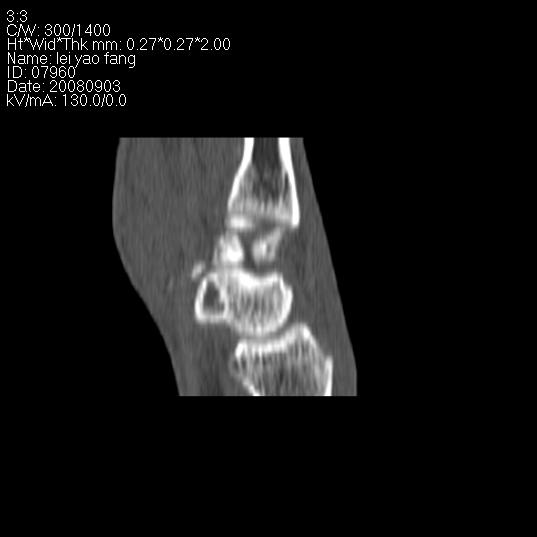

以下是引用杀毒软件在2008-9-4 17:41:00的发言:[br]考虑----舟骨囊肿